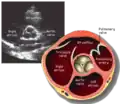

Parasternal short axis (PSAX)

This view is obtained in the same window as the parasternal long, but with the probe rotated 90°. In this view, the aortic valve is seen in cross-section with the right ventricular inflow & outflow tracts visible with the tricuspid valve as well. Pulmonary valve is not visible in this view. Both the right and left atria are visible.

The standard PSAX view is at the level of the aortic valve, but moving the probe along the long-axis can review the LV outflow tract, LV at the base, and LV at the midsection.

Structures visible:

- Aortic valve in short-axis

- Aortic valve dysfunction, aortic sclerosis/stenosis

- Tricuspid valve in long-axis

- Pulmonary valve in long-axis

- Right ventricle, including inflow and outflow tracts

- Left ventricle in short-axis

- Closer to the base can reveal the left ventricular outflow tract

- At the level of the base can show the movement of the mitral valve leaflets in short-axis

- At the level of mid-LV can show papillary muscles